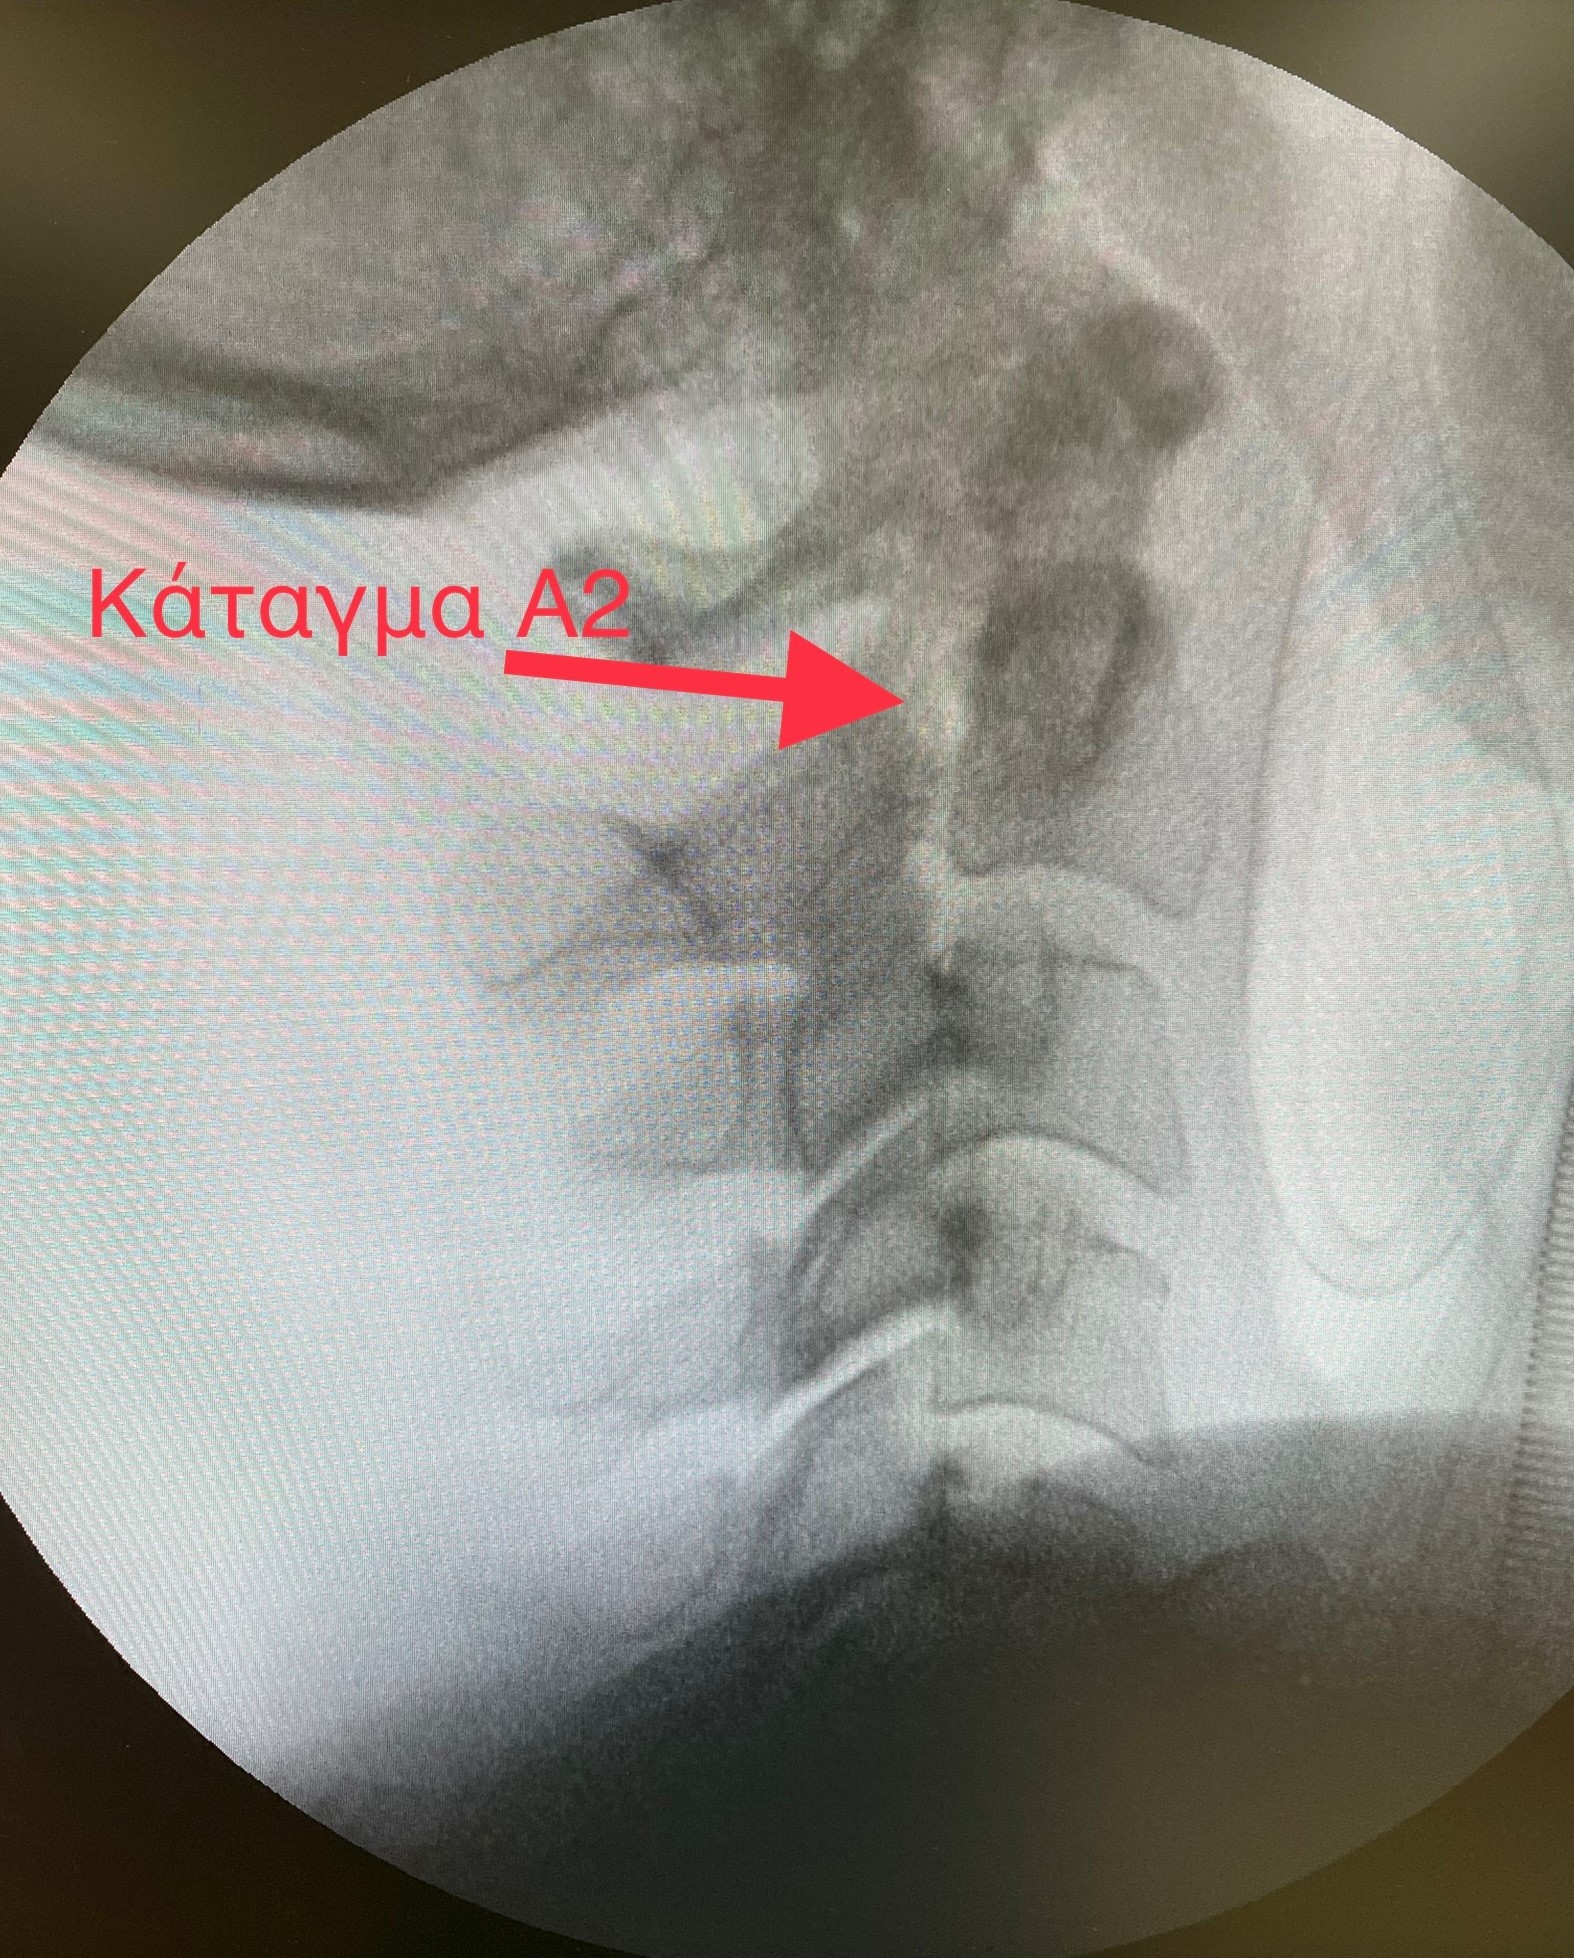

Ασθενής 53 ετών με κάταγμα στο δεύτερο αυχενικό σπόνδυλο (Hangman fracture) μετά από τροχαίο ατύχημα αντιμετωπίστηκε χειρουργικά από την Β΄ Νευροχειρουργική Κλινική του ΙΑΣΩ Θεσσαλίας.

Αφού διενεργήθηκε ο απαιτούμενος κλινικοεργαστηριακός έλεγχος διαπιστώθηκε ότι υπάρχει αστάθεια της ανώτερης αυχενικής μοίρας της σπονδυλικής στήλης και κρίθηκε απαραίτητη η διενέργεια χειρουργικής επέμβασης.

Η επέμβαση έγινε με οπίσθια αυχενική σπονδυλοδεσία τοποθετώντας διαυχενικούς κοχλίες στον Α2 σπόνδυλο και κοχλίες στα πλάγια ογκώματα του Α3 σπονδύλου (transpedicular screw and lateral mass), προσφέροντας πλήρη σταθεροποίηση του κατάγματος.